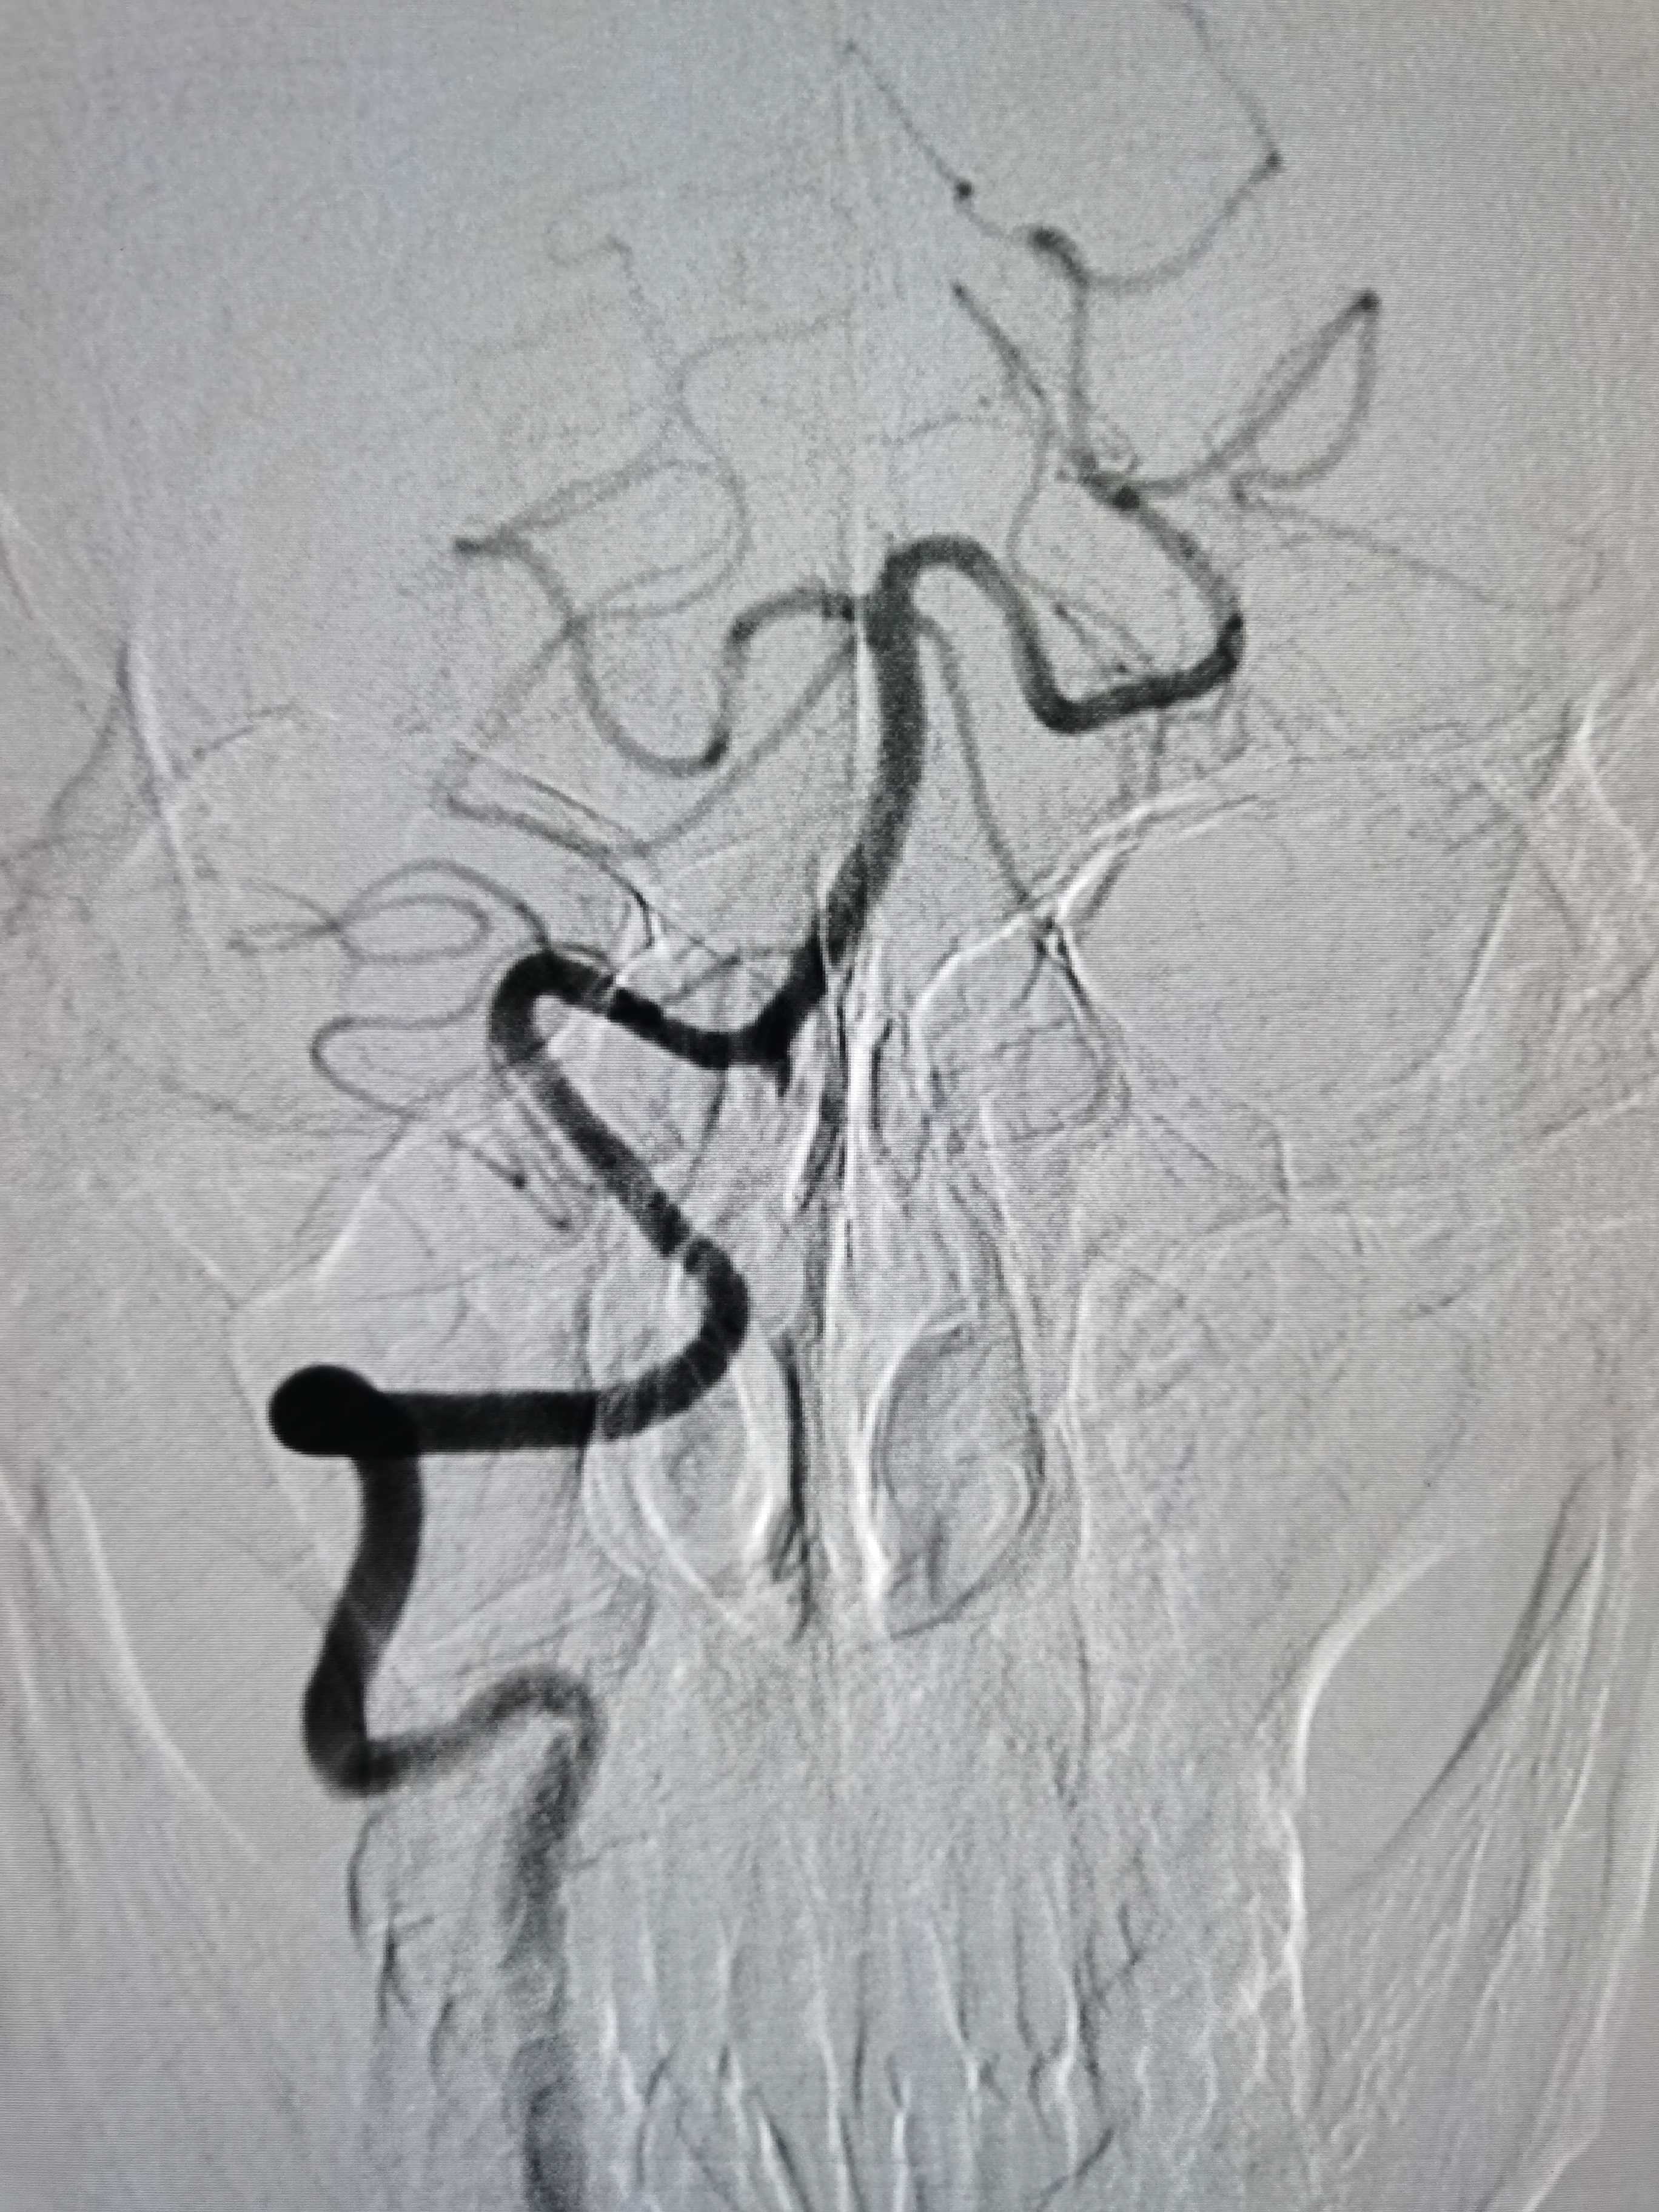

将8F导引导管送至左侧锁骨下动脉近左椎动脉起始部,微导丝顺利通过病变,2.0/20球囊预扩病变。

2、CTA证实左椎动脉起始部重度狭窄合并血栓,系责任血管,存在急性闭塞或残存血栓脱落至基底动脉风险,需积极处理。

3、手术过程中,先用小球囊扩张病变,观察血栓情况,及时应用支架全程覆盖血栓及病变部位,成形满意。